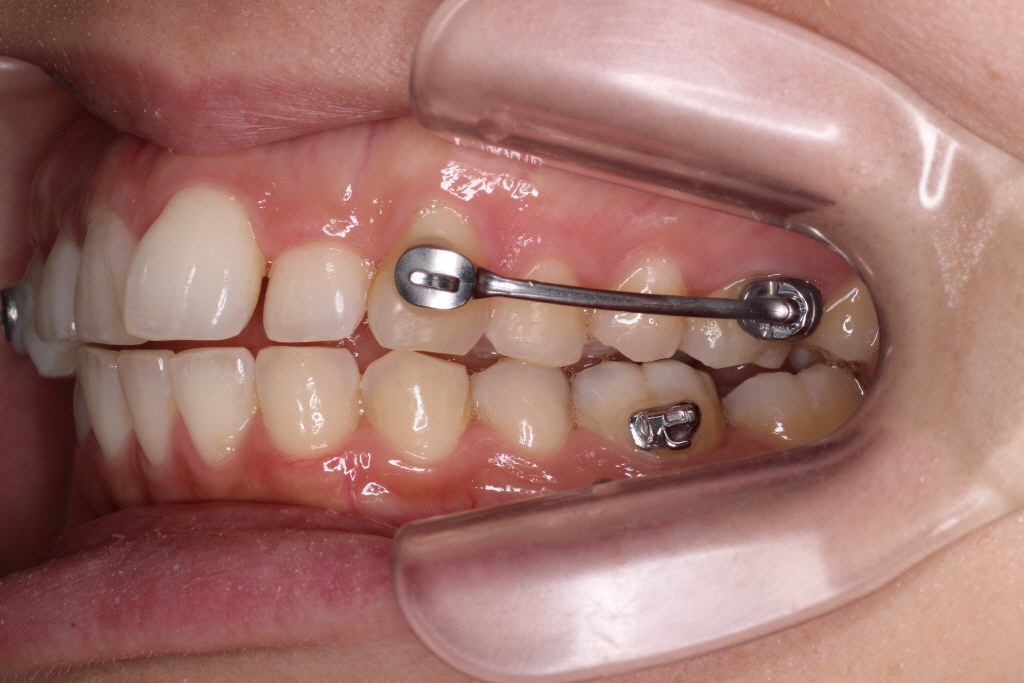

インビザラインでゴムかけする場合は、写真のような方法でゴムかけをします。

(こちらの写真は当院スタッフの口腔内です)

下の奥歯にボタン(ゴムをかける為のフック)をつけ固定します。

上のマウスピースはゴムがかけられるような仕組みになっているので

下のボタンと上のマウスピースにゴムをかける事で遠心力で上の奥歯を後ろにさげます。